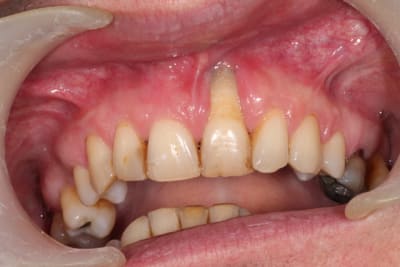

Patient adressé par une consœur pour sa 21. Fume un paquet.

Pas vraiment de pb paro, à part un bourrage entre 26 et 27 ayant entrainé une perte osseuse conséquente.

Grosse supra.

1 : Pensez vous que la cause de la lésion soit occlusale, justement ( cela aurait pu débuter comme sur la 11, flèche rouge ) ?

2 : quid de la jonction avec le canal nasopalatin ( flèche verte ) ?

3 : après extraction, grosse perte tissulaire a prévoir. si reconstruction osseuse, il n'y aura pas un problème de tissus mou ? , faut il épaissir et faire une greffe de conjonctif avant greffe osseuse ?